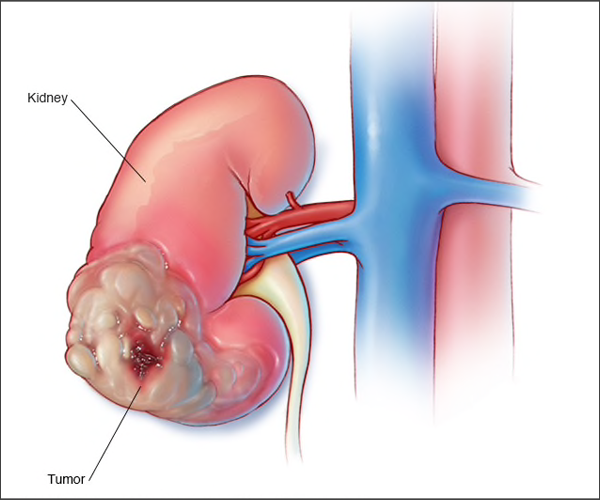

TUMOR AT LOWER POLE OF RIGHT KIDNEY

Renal cell carcinoma is the most common type of kidney cancer in adults, which accounts for about 90 percent of malignant tumors of the kidney & is the most lethal of the common urologic cancers. This begins in the cells of kidney. Other less common types of kidney cancer can occur. Young children are more likely to develop a particular type of kidney cancer called Wilms' tumor. Because of the location of the kidney within the retroperitoneum, many kidney masses remain asymptomatic and non-palpable until they are locally advanced. The incidence of kidney cancer seems to be increasing. With the more prevalent use of non-invasive imaging techniques such as computerized tomography (CT) scans for the evaluation of a variety of nonspecific symptoms, more than 60% of kidney cancers are now detected incidentally. In many cases, kidney cancer is found at an early stage, when the tumors are small and confined to the kidney, making them easier to treat.